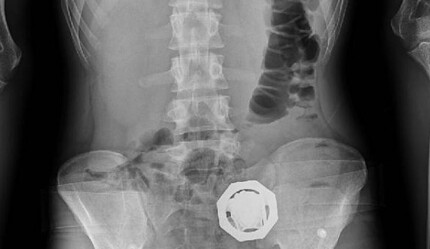

16 Haziran 2023 tarihinde yapılan operasyonla ilgili, “Hedef şahısların ev ve iş yerlerinde yapılan arama neticesinde 510 gram metamfetamin, 550 gram esrar, 3 adet uyarıcı hap, 1 adet hassas terazi, 1 adet ruhsatsız pompalı tüfek, 1 adet havalı tabanca, 1 adet kurusıkı tabanca, 1 adet 9 mm tabanca fişeği ele geçirildi” şeklinde bir açıklama yapılmıştı.